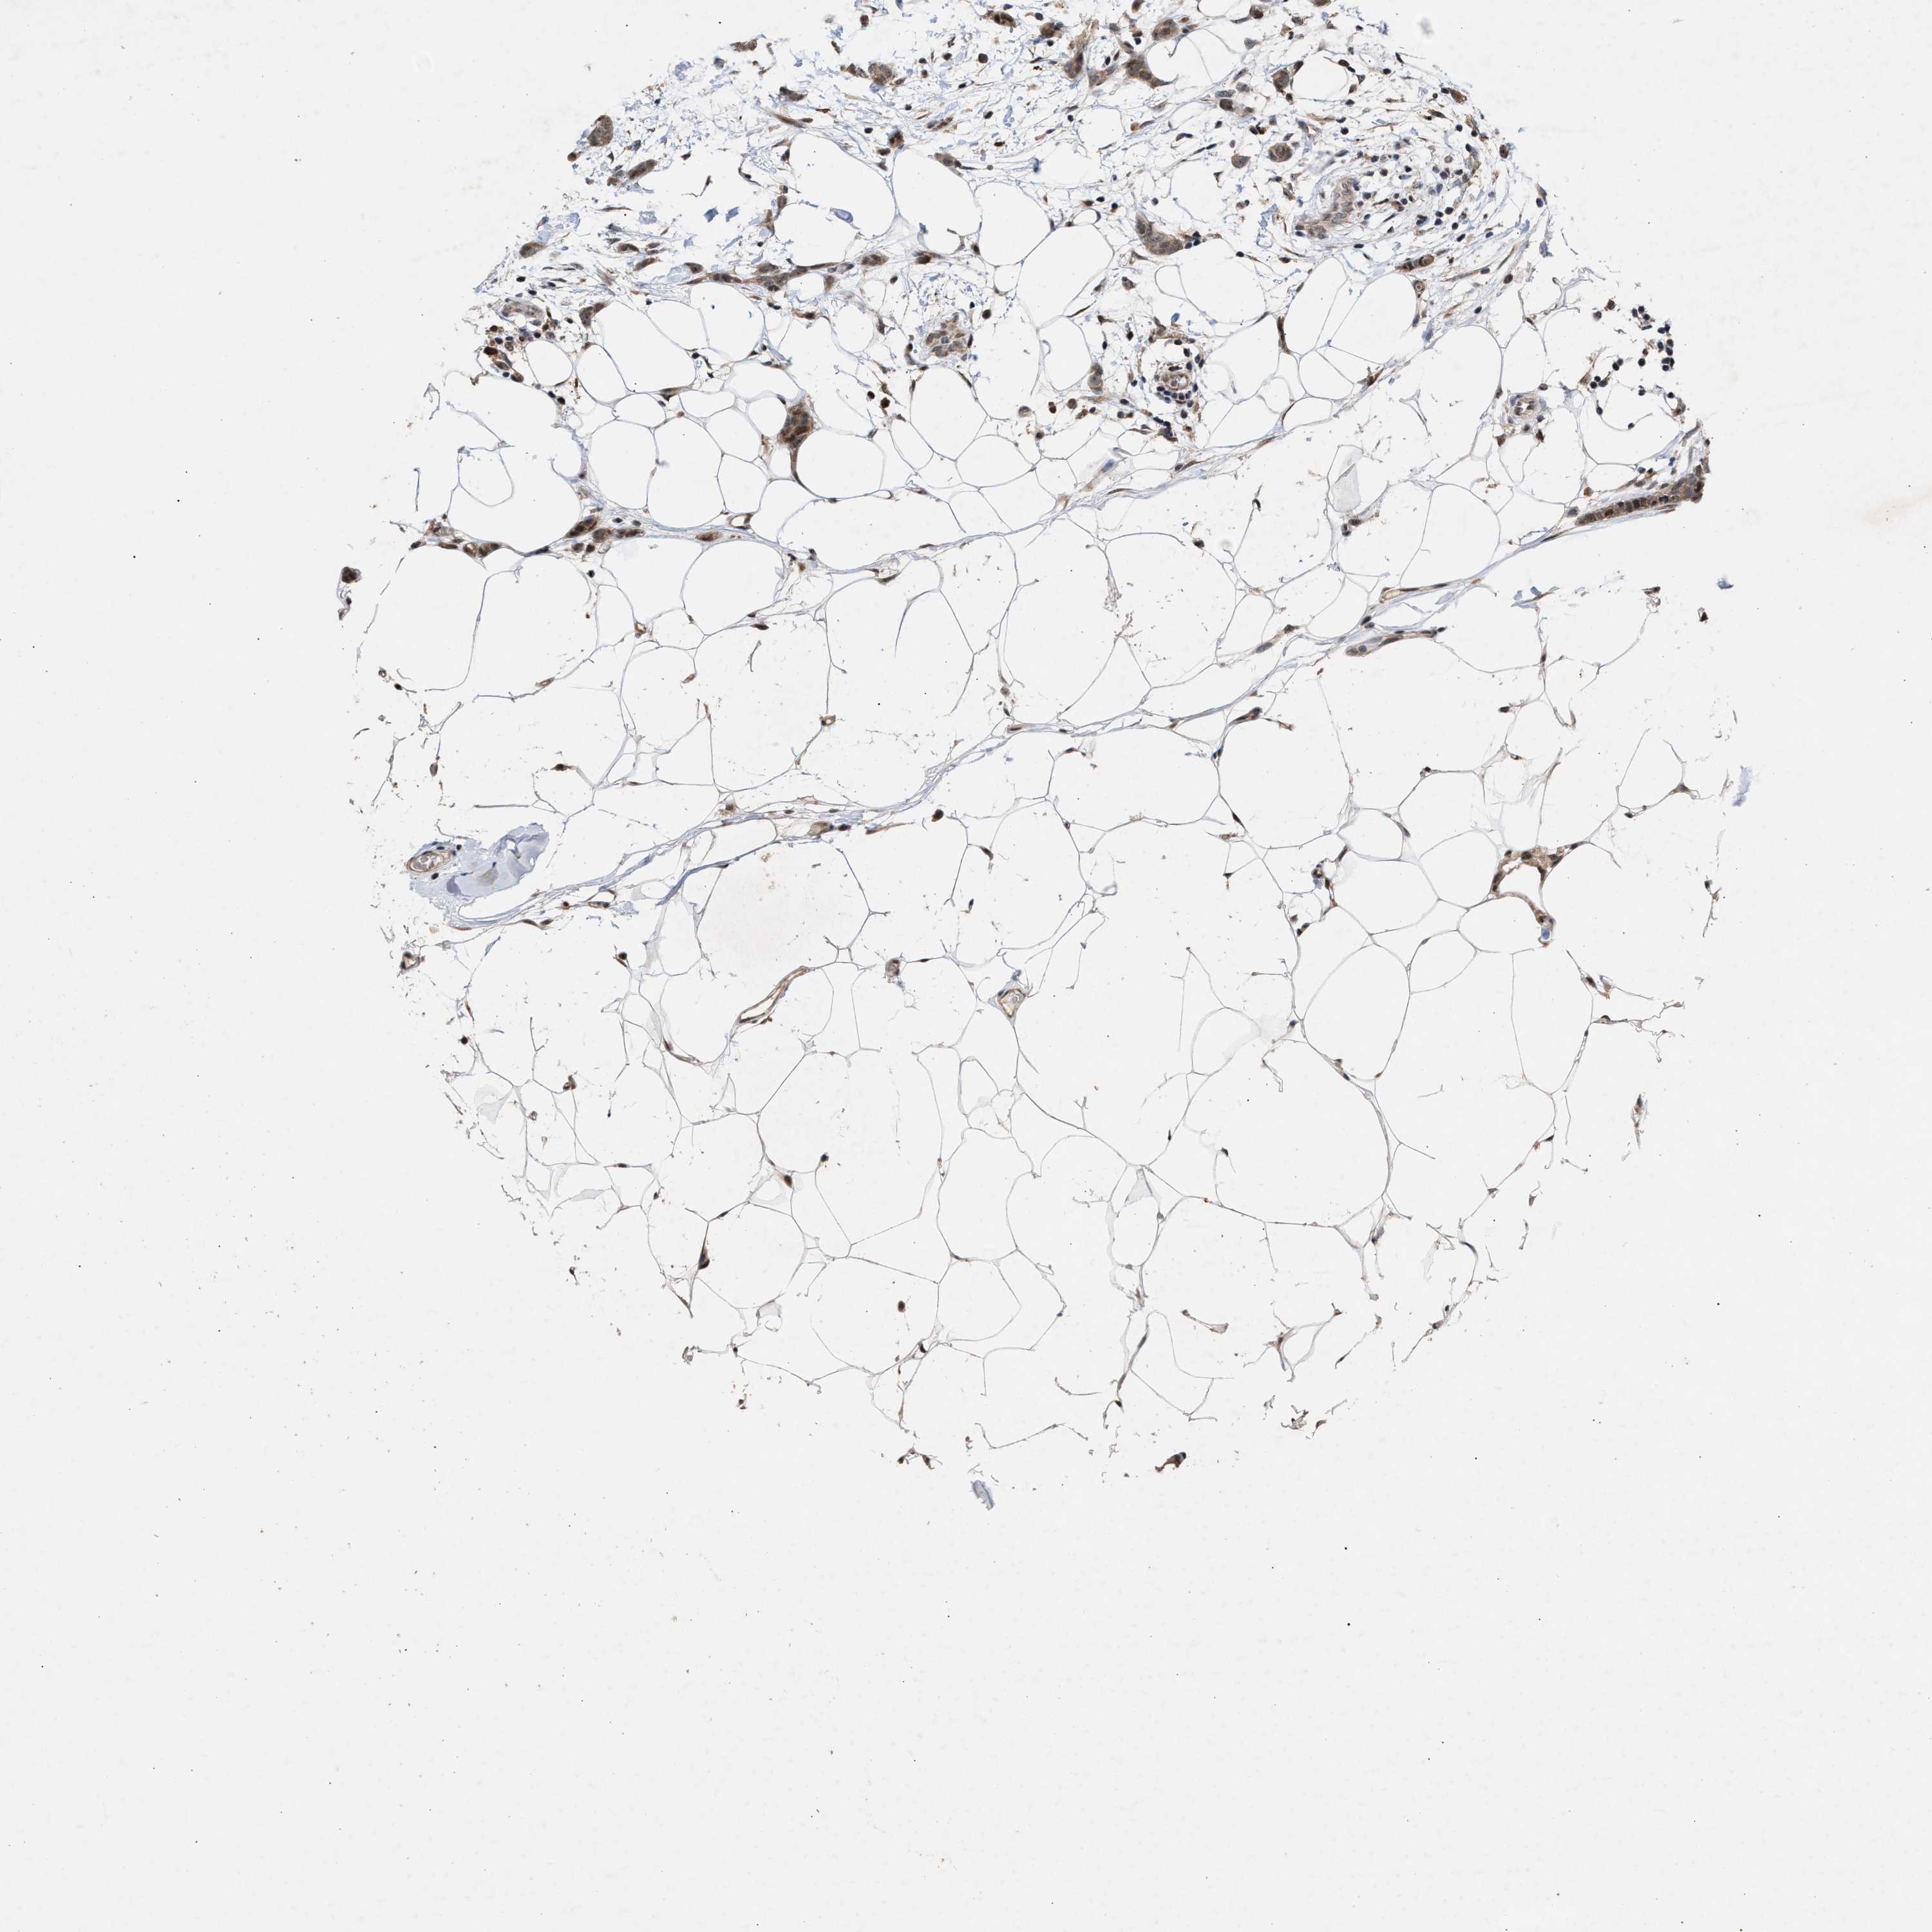

BRCA TCGA BRCA VALIDATION PROTEIN EXPRESSION

Breast cancer

Human cancer

Breast invasive carcinoma